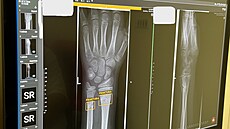

A jak taková spolupráce AI a lékaře vypadá v praxi? Systém AI mají lékaři v programech, v nichž si prohlížejí snímky pacientů. Snímek z nemocnice v anonymizované podobě následně pošlou do společnosti, která systém provozuje.

„Umělá inteligence obraz vyhodnotí a predikce zašle zpět do počítače vyšetřujícího lékaře. Snímky jednotlivých pacientů roztřídí podle míry podezření na patologický nález. Výstupem u každého snímku je grafická lokalizace nálezu spolu s určením typu patologie,“ popsal primář Markvart.